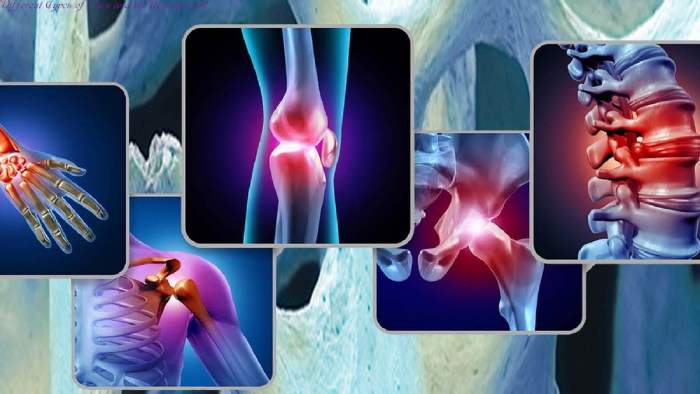

Different Types of Pain and its Management

Different Types of Pain and its Management